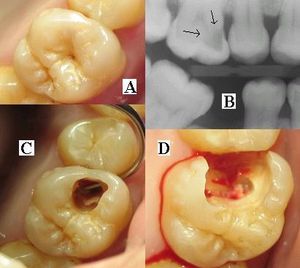

충치 초기에는 통증이 거의 없으며, 치아 표면에 흰색 반점이나 갈색의 착색이 나타날 수 있다. 이를 백색 반점 병변, 초기 충치 병변 또는 "미세 공동"이라고 부르기도 한다.[13] 충치가 진행됨에 따라 차갑거나 뜨거운 음식, 단 음식에 시린 증상을 느끼거나, 음식물을 씹을 때 통증을 느낄 수 있다.[276][277] 이는 상아세관이 노출되어 나타나는 증상이다.[15]

치과 검진 시에는 육안 검사, 치과 탐침을 이용한 촉진, 방사선 촬영 등을 통해 충치를 진단한다.[88] 특히, 치아 사이의 충치나 초기 충치는 방사선 사진을 통해 확인하는 것이 유용하다.[88]

치아는 지속적으로 형성되는 박테리아 코팅(생물막)에 의해 덮여 있다. 이 생물막이 성숙하면서 치아 표면에 충치를 유발하는 환경이 조성된다.[73][74] 충치는 발생 부위, 병소의 형태, 진행 정도 등에 따라 다음과 같이 분류된다.- 소와 열구 우식: 어금니 씹는 면의 홈과 틈새(소와 열구)에 발생하는 충치이다. 이 부위는 세척이 어렵고 음식물 찌꺼기가 쌓이기 쉬워 충치가 많이 발생한다.

- 평활면 우식: 치아 옆면이나 치아와 잇몸 경계 부위에 발생하는 충치이다. 인접면 우식은 X선 촬영으로 확인되는 경우가 많다.

C0 단계는 치아 표면에 불투명감이나 백반, 색소 침착이 보이지만, 우식(구멍)은 확인되지 않는 초기 상태이다.[276][277]C1 단계는 법랑질에 국한된 충치이다.[276][277] 이 단계에서는 충치 부위를 긁어내고 레진으로 덮는 간단한 치료를 할 수 있다. 통증이 거의 없어 정기검진을 통해서만 주로 발견된다.[276][277]

C2 단계는 상아질까지 진행된 충치이다.[276][277] 차거나 뜨거운 것에 시린 증상을 느끼고, 심하면 음식물을 씹을 때 통증을 느낀다.[276][277] 충치 부위를 삭제하고 빈 공간을 레진 인레이나 골드 인레이로 채워 넣는 치료가 필요하다.[276][277]